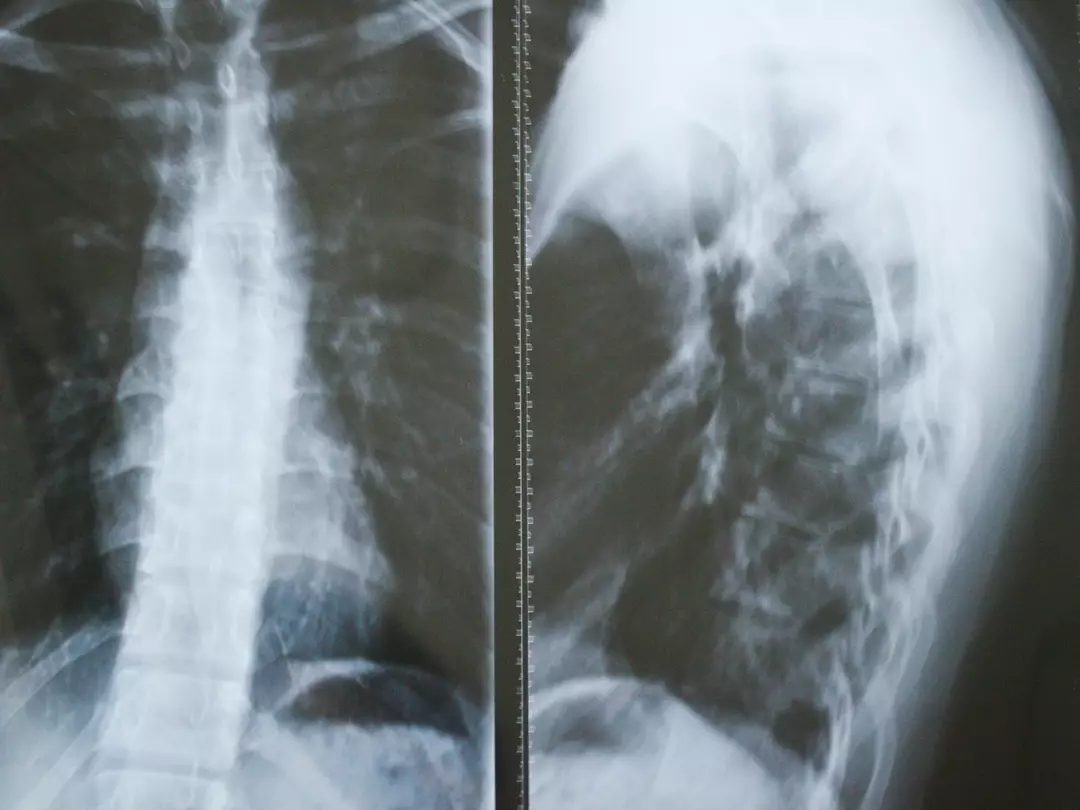

GSS is marked by gradual bone deterioration, where normal bone is eroded and substituted by unusual lymphatic and fibrous tissue. Despite years of study, its exact cause remains unidentified, leaving specialists confused.

Gradually, the body inadvertently replaces hard bone with soft tissue, resulting in weakening, deformity, or total disappearance of the affected bone.

Healthcare professionals depend on imaging scans to monitor bone loss and usually confirm the condition through a bone biopsy, which reveals non-cancerous vascular tissue replacing bone.